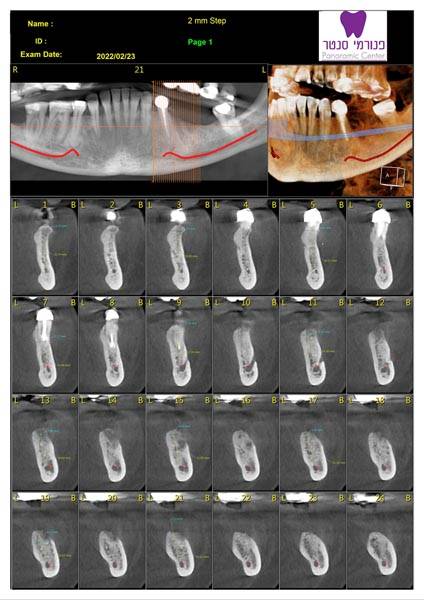

זקוקים לצילומי שיניים וחשוב לכם לקבל מענה מקצועי, אמין, מהיר ויעיל? מכון פנורמי סנטר לשירותכם! כמכון רנטגן מוביל בתחומו, אנו מבצעים צילומי שיניים ולסתות לרבות צילומי CT ואמונים על מתן שירות מקצועי, אדיב, אישי ויעיל לכל לקוח ולקוח. לנוחיותכם, אנו מספקים את מיטב שירותינו באמצעות שלושה סניפים לרבות סניף ברמת ישי, סניף ביוקנעם וסניף במגדל העמק ונשמח לעמוד גם לשירותכם לשביעות רצונכם המלאה!